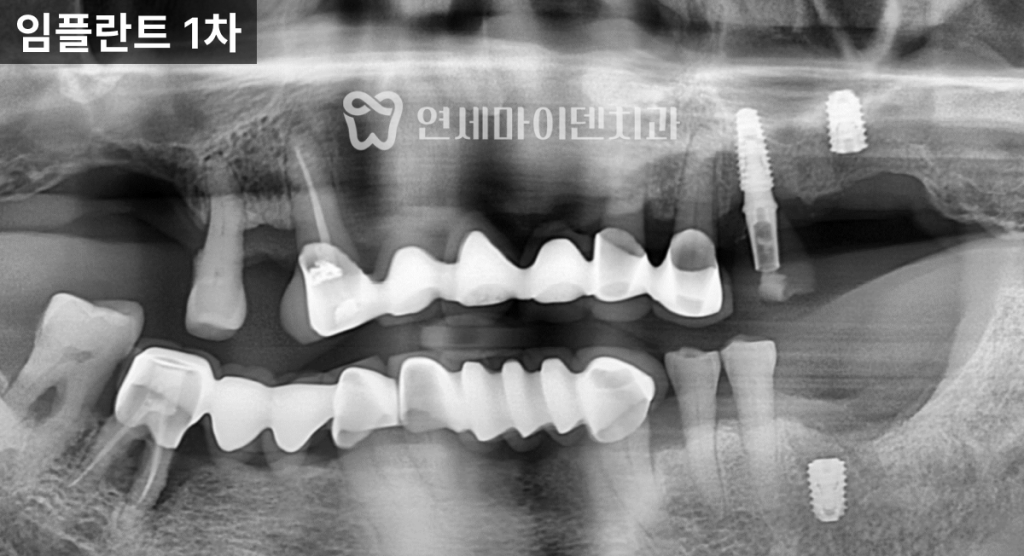

첫째는 충분한 뼈 이식,

둘째는 임플란트 식립 깊이였습니다.

기존 임플란트를 제거한 부위는

골 결손이 컸기 때문에,

단순히 임플란트만 다시 심는 것으로는

장기적인 안정성을 기대하기 어려웠습니다.

그래서 비교적 적극적으로 뼈 이식을 진행했습니다.

또 하나는 임플란트를

뼈 레벨보다 약간 깊게 식립해,

보철물과 임플란트 경계 부위에

일정 공간을 확보하는 것이었습니다.